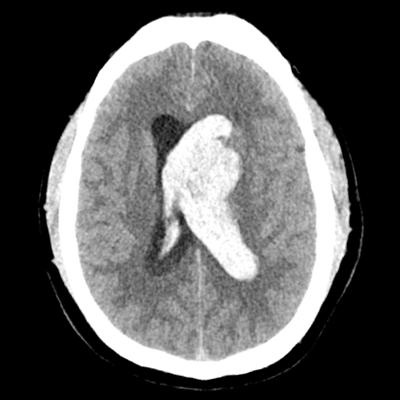

HCT showing L caudate IPH with IVH HCT showing L caudate IPH with IVH

A 43 year-old man with HTN presents to the ED with an acute onset of word-finding difficulties, dysarthria, and right hemiplegia. Initial vitals are notable for BP 195/98, HR 97, RR 12, T 37.2C. Labs identify no coagulopathy. He takes no medications. He gets a non-contrast head CT, as shown here. You note that he has a casted left lateral ventricle (IVH) along with a left caudate IPH. The patient experiences a sudden decline in mental status and requires intubation for airway protection. The ED gives him IV labetalol 10mg and starts him on nicardipine gtt to achieve goal SBP < 140. What is the best next step in management for this patient?

This is definitely a measure worth consideration throughout his early clinical course, though is not currently indicated for this patient. He has a large hematoma burden, but it's primarily intraventricular, with some within the adjacent parenchyma in the left caudate. (He likely first had a hypertensive bleed within the caudate that dissected into the ventricular system.) The IPH isn't producing any significant mass effect to necessitate decompression.

Yes! The patient has likely developed obstructive hydrocephalus due to the IVH that is casting the left lateral ventricle. This is a larger contributor to his neurologic decline than any mass effect you can see from the caudate bleed. He needs CSF diversion via an EVD.